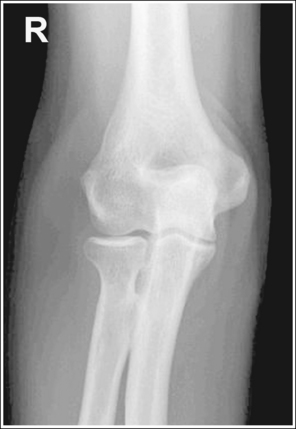

The elbow is positioned in an AP projection. The medial and lateral humeral epicondyles are demonstrated in profile at the extreme medial and lateral edges of the distal humerus, and the radial head is superimposed over the lateral aspect of the proximal ulna by approximately 0.25 inch (0.6 cm). The coronoid process is demonstrated on end.

• An AP projection of the elbow is obtained by supinating the patient's hand and externally rotating the forearm and humerus until an imaginary line drawn between the humeral epicondyles is parallel with the IR (Figure 4-67). This positioning places the proximal radius anterior to the ulna.

• Detecting elbow rotation. Rotation of the elbow is a result of poor humeral epicondyle positioning and can be identified on an image when (1) the epicondyles are not visualized in profile, (2) the radial head is demonstrated with more or less than 0.25 inch (0.6 cm) superimposition of the ulna, and (3) the coronoid process is seen in profile. The smaller, lateral humeral epicondyle is more sensitive to rotation, moving out of profile with only a slight degree of elbow rotation. If the epicondyles are not demonstrated in profile, evaluate the degree of radial head superimposition of the ulna to determine how to reposition for an AP projection. If more than 0.25 inch (0.6 cm) of radial head is superimposed over the ulna, the elbow has been internally rotated (see Image 74). If less than 0.25 inch (0.6 cm) of the radial head is superimposed over the ulna, the elbow has been externally rotated (see Images 75 and 76).